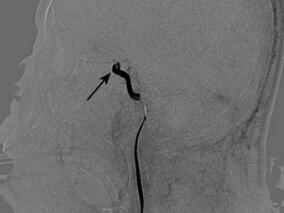

1小时条评论1 病例简介 患者男,40岁,主因突发左侧肢体无力2小时于2011年3月30日入院。患者2小时前安静状态下无明显诱因出现左侧肢体无力,伴言语不清、不能行走、意识模糊。无视物旋转、视物成双、耳鸣、恶心、呕吐,无饮水呛咳及吞咽困难,无流涎,无肢体抽搐,无大小便失...